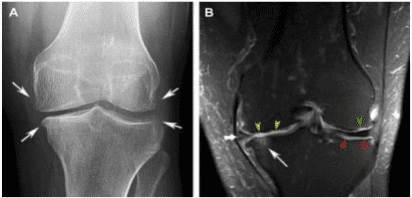

Imaging of Osteoarthritis in the knee (Hunter DJ (1999)4 Fig 1).

Image A: Image of a healthy knee. Notice the well-preserved joint space, contrast of the bone, healthy soft tissue (muscles), the absence of bone spurs, and bony outgrowths.

Image B: Imagine of a knee with osteoarthritis: Notice the narrowing of joint space, the presence of bony spurs along the joint and the presence of adipose (fat) in the atrophied muscles.